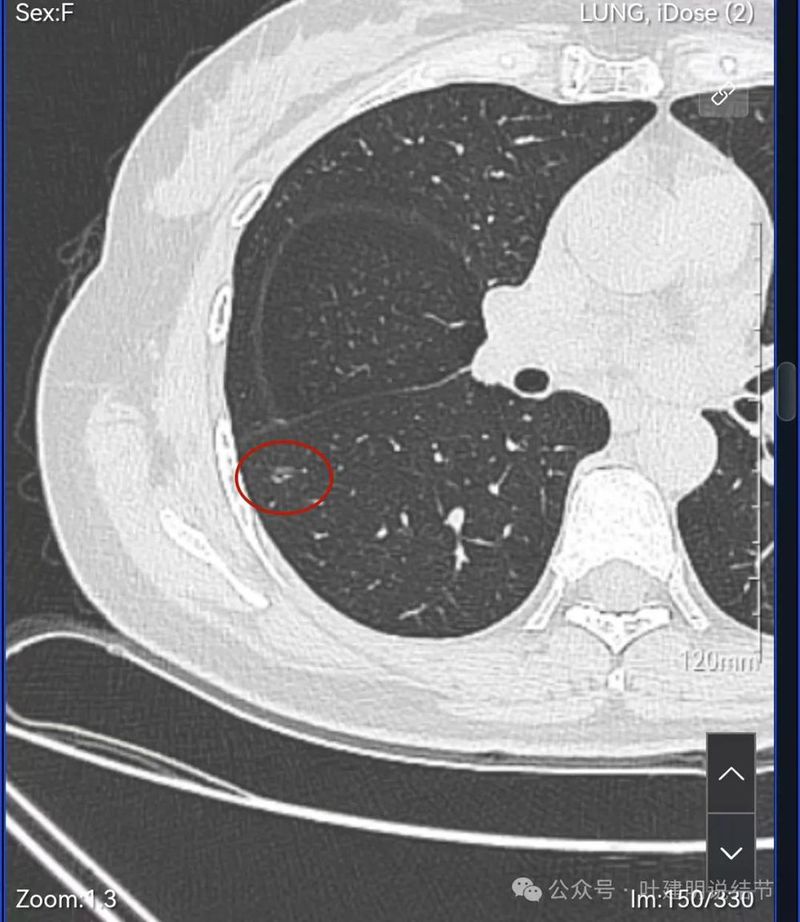

病灶3:右下叶混合密度结节,轮廓清,紧贴叶裂,伴有叶间胸膜牵拉,内部密度显杂乱,表面有分叶。

此灶分叶明显,灶内有小空泡征,有血管穿行,整体轮廓与边界清楚。

病灶出现,紧贴叶间裂。

轮廓清楚,叶间胸膜牵拉。

密度不太纯,轮廓与边界清。

表面分叶,中间空泡,边缘有磨玻璃成分,叶间胸膜凹陷。

灶内血管穿行,表面分叶、中间空泡,实性成分。

血管进入,表面分叶,密度不均。

密度显杂乱,血管贴边。

细毛刺或小棘突,表面不平。

边缘区磨玻璃密度,有微小血管贴着。

右肺多发磨玻璃结节,红色的是主病灶,密度不纯,贴着叶间裂,分叶明显,考虑至少微浸润性腺癌,也可能是浸润性腺癌贴壁为主型,不能继续随访,建议手术切除,可以单孔胸腔镜下局部楔形切除。黄色的也是磨玻璃,不典型增生或者肺泡上皮增生可能性大,蓝色的肺泡上皮增生可能性大。这两处风险还低,但如果主病灶需要处理,也可以考虑同期切除。意见供参考!